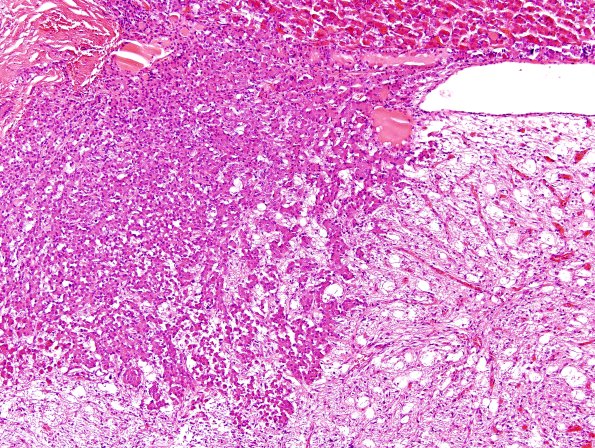

Washington University Experience | NORMAL | Pituitary gland | 6A2 Pituitary, Normal Gland H&E 2

The posterior pituitary often shows an apparent “invasion” by basophils which is a normal variation which may cause some confusion with metastatic spread to the pituitary and usually do not form normal acini. (H&E)